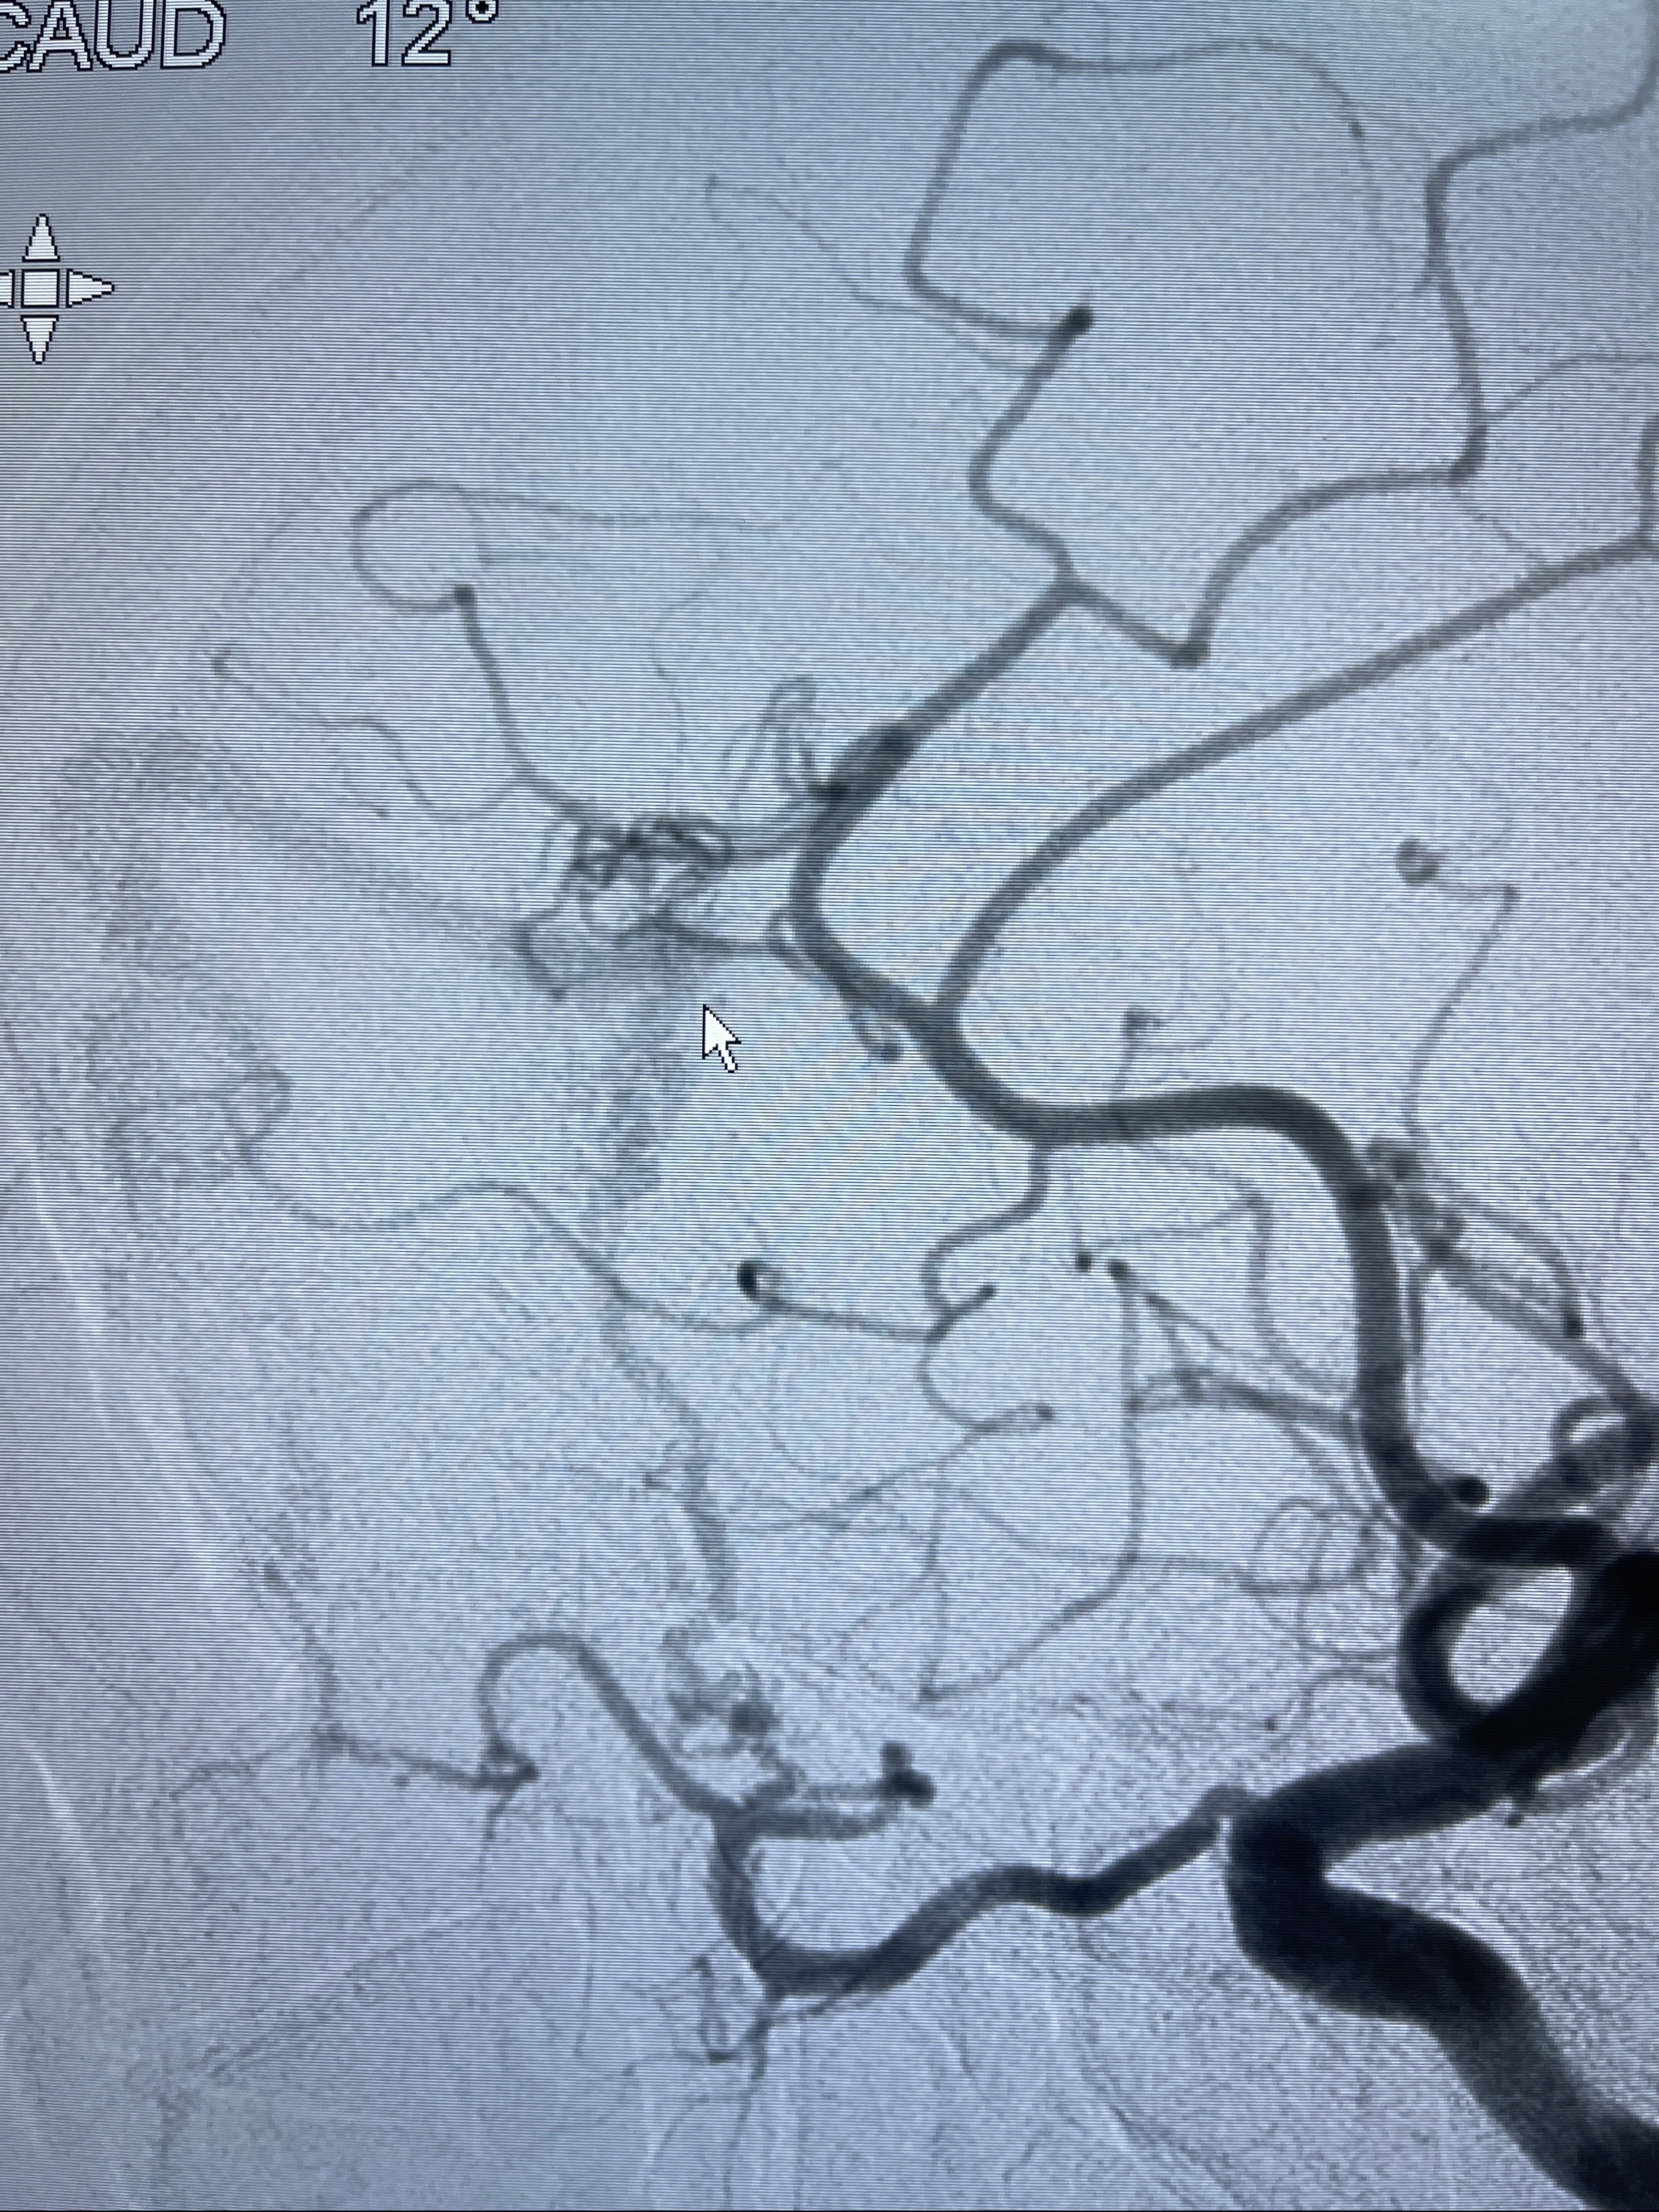

2023-09-13全脑血管造影:前颅底硬脑膜动静脉瘘,供血动脉为双侧胼周动脉、眼动脉脑膜支,静脉向上矢状窦方向引流

- 介入干预:静脉途径栓塞or动脉途径填塞?